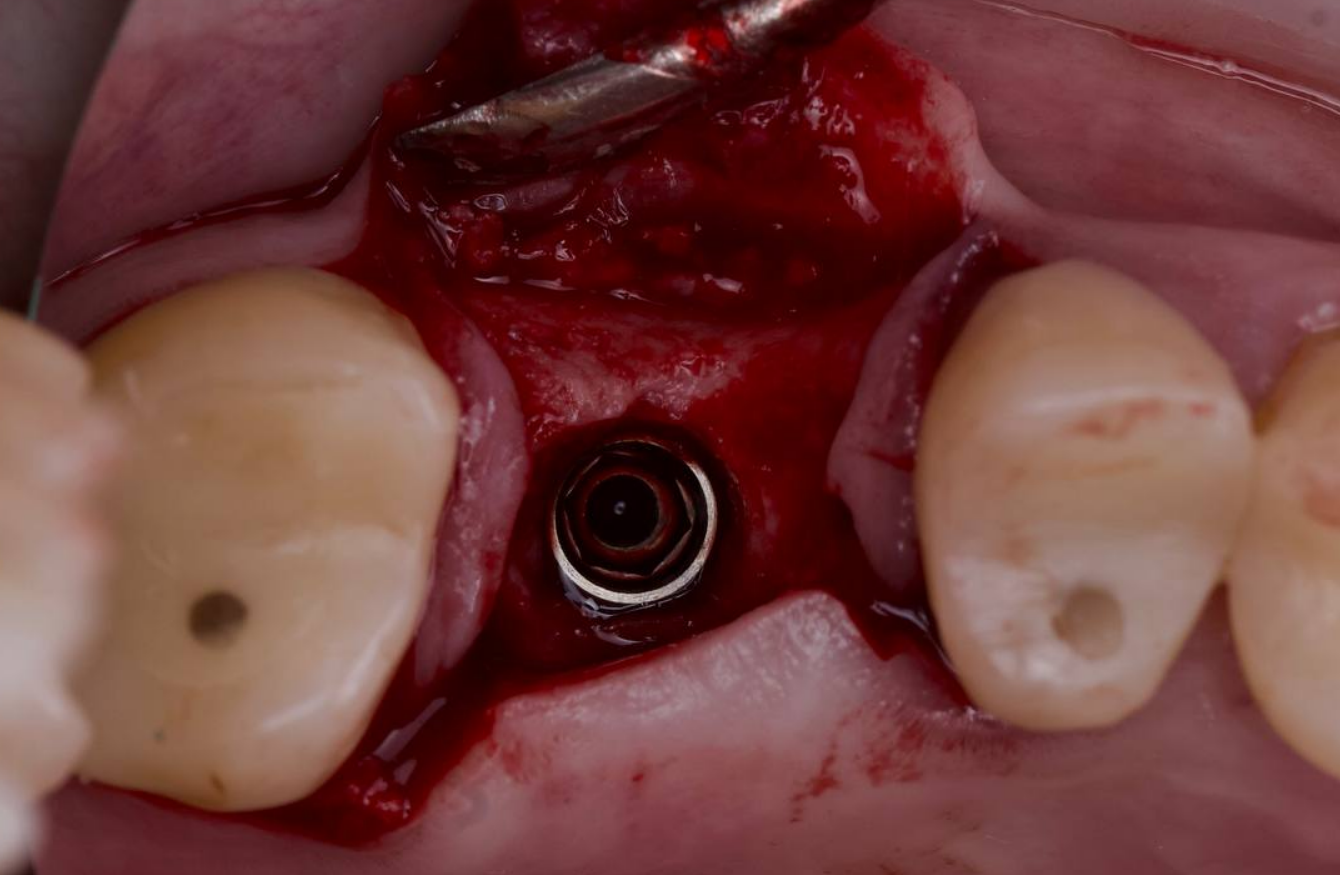

ЗСЛ + имплантация

Закрытый синус-лифтинг, выполненный вогнутым остеотомом, с показательным срезом КТ после операции.